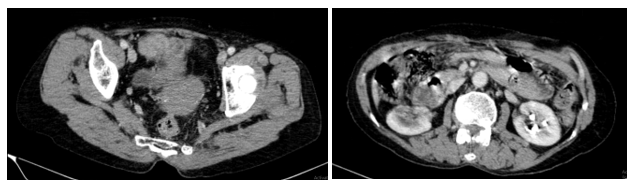

Hình 10: Chụp CT ổ bụng có tiêm thuốc cản quang sau điều trị không phát hiện dịch ổ bụng, không phát hiện hình ảnh dày phúc mạc khu trú.